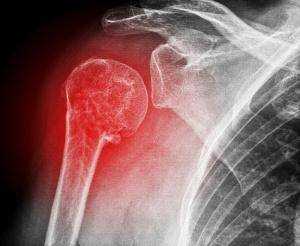

На снимках плечевого сустава хорошо видны головка плечевой кости, суставная впадина лопатки, плечевой отросток лопатки.

На рентгенограмме, произведенной в условиях супинации кисти, хорошо виден большой бугорок плечевой кости, который здесь является краеобразующим (рис.312, 313). На снимках, произведенных в условиях пронации кисти, большой бугорок виден хуже, но по медиальному контуру над хирургической шейкой становится виден малый бугорок (рис.314). Медиальный и латеральный контуры тела плечевой кости при этих двух вариантах укладки на снимках образованы разными ее поверхностями. На снимке при супинации кисти медиальный контур образован внутренней, а латеральный — наружной поверхностью тела плечевой кости; на снимке при пронации кисти медиальный контур отображает переднюю, а латеральный — заднюю поверхность тела плечевой кости.